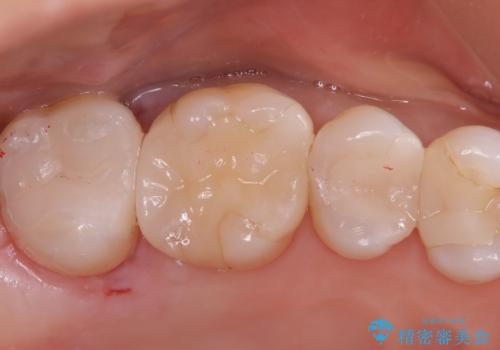

フロスなどの日常の清掃はもちろん不可欠ですが、メタルインレーより汚れが付着しずらいセラミックインレーにて今回は治療を行いました。

セラミックインレー装着時はラバーダムを使用して行っています。